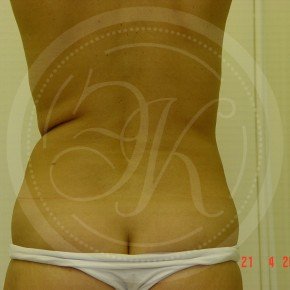

Фото до и после липосакции

В этой галерее мы публикуем снимки тех пациентов, которым была проведена липосакция. Фото до и после в полной мере позволяют оценить результат. Для каждого пациента мы подбираем тот вид вмешательства, который даст лучший результат при минимальном травматизме.